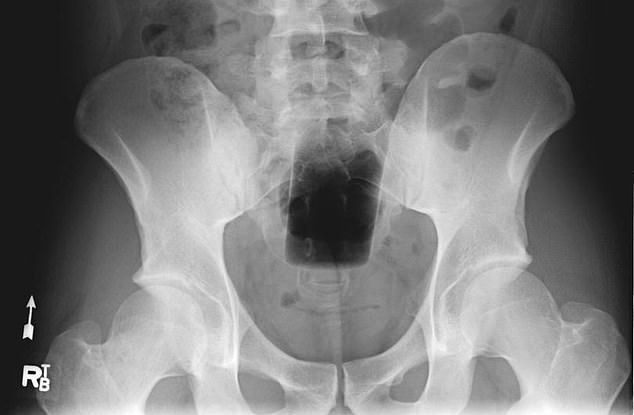

Every year, Americans end up with different types of objects stuck in their rectums.

It was found that the rectum is the most common place for bizarre items to get stuck. Some of the objects include household items such as aerosol can, plastic pill bottle, beer bottle, and a plastic cigar holder.

Other articles such as a ‘leg of a telescope’, ‘cell phone’ and ‘Christmas ornament ball’ have also been found in some patients.